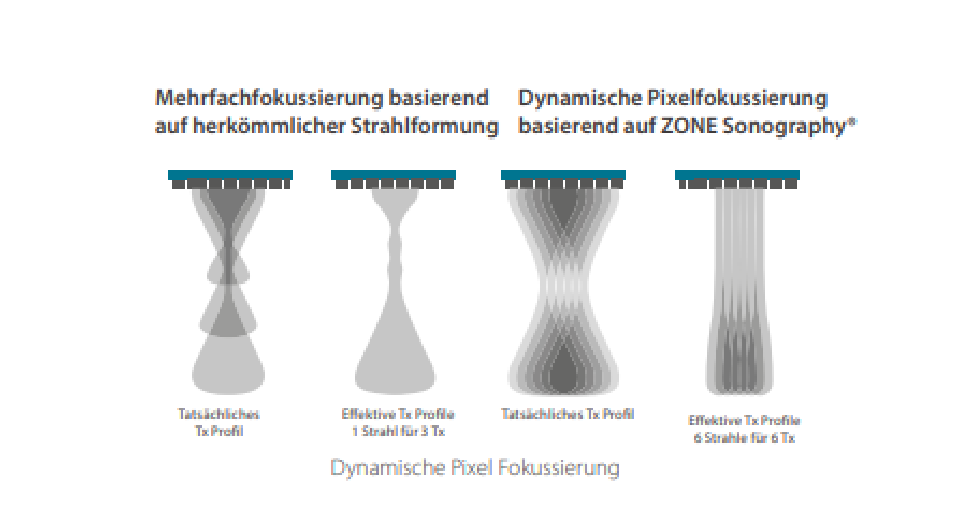

Dank der ZONE Sonography?-Technologie (ZST+) wird das B-Bild des Resona 7 ├╝ber die komplette Tiefe fokussiert, sodass keine Fokuspunkte mehr gesetzt werden m├╝ssen. Die Schall-Lauf-Geschwindigkeit (SSC) wird auf Knopfdruck individuell auf den Patienten angepasst, was die Darstellung von Organen, Grenzfl?chen und Gewebever?nderungen erheblich verbessert. Und dank der fortschrittlichen iFusion-Funktion k?nnen optional die Daten von Ultraschall-, MRT-und CT-Bildern synchronisiert werden.